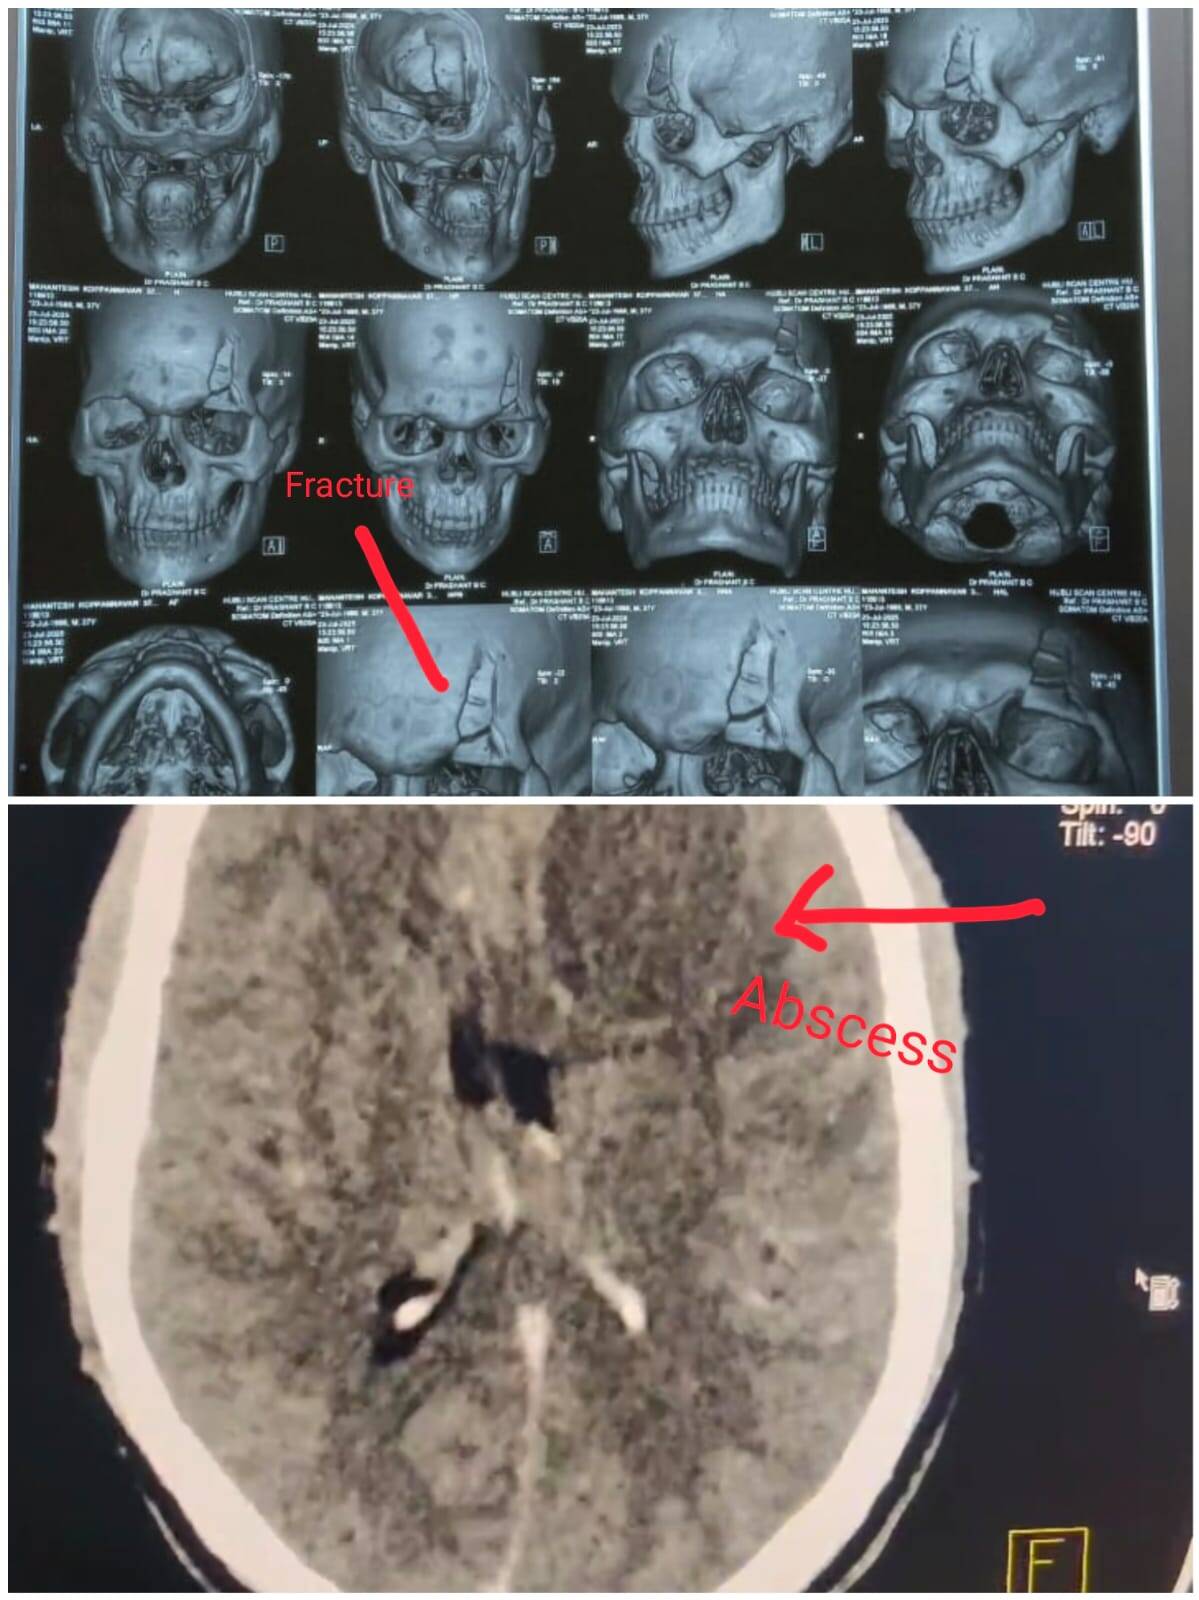

A CT scan of the brain revealed:

Frontal bone fracture

Underlying brain abscess – a rare but dangerous infection inside the brain tissue, often caused by trauma or poor wound care.

ಮುಂಭಾಗದ ಅಸ್ಥಿ ಮುರಿತ

ಮೆದುಳಿನ ಪುಟ್ಟಬೂದಿ (Abscess) – ಅಪರೂಪವಾದರೂ ಅಪಾಯಕಾರಿ ಸೋಂಕು, ಸಾಮಾನ್ಯವಾಗಿ ಗಾಯ ಅಥವಾ ತೊಂದರೆಗೊಂಡ ಗಾಯದ ಆರೈಕೆ ಕೊರತೆಯಿಂದ ಉಂಟಾಗುವುದು.